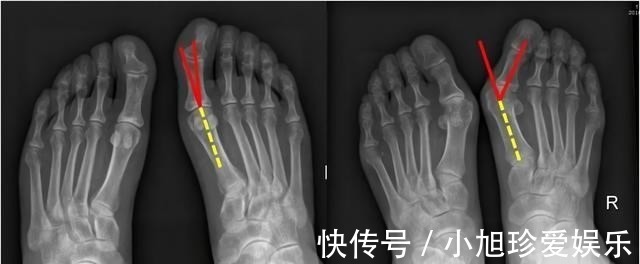

高跟鞋的后跟要比鞋尖高出许多,而且鞋尖非常窄,这对于人体正常的脚是非常不合理的,首先高跟鞋穿起来必然会对脚的大拇指造成挤压,久而久之就会导致拇指外翻,而且由于脚拇指受到挤压,这就会加大患上拇囊炎的几率。

其次,穿上高跟鞋之后,由于脚掌倾斜,这样不可避免会造成骨盆前倾且收窄,还会影响到腰部,造成腰椎间盘突出,大家都知道我们人类一直以来都是靠着脚前掌内、脚前掌外以及脚后跟这三点支撑起来的,但穿上高跟鞋之后,原来的三点支撑就会变成两点支撑甚至一点支撑,人体全部体重都得靠脚趾和脚掌的关节支撑,时间一长,轻则受压迫的脚前掌长鸡眼,重则引发拇囊炎。